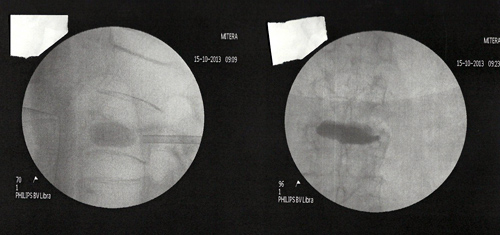

Σε περιπτώσεις πρόσφατης παραμόρφωσης (κάταγμα) που φαίνεται στην μαγνητική τομογραφία, εγχύουμε ακρυλικό τσιμέντο (κυφοπλαστική) για στήριξη του σπονδύλου.